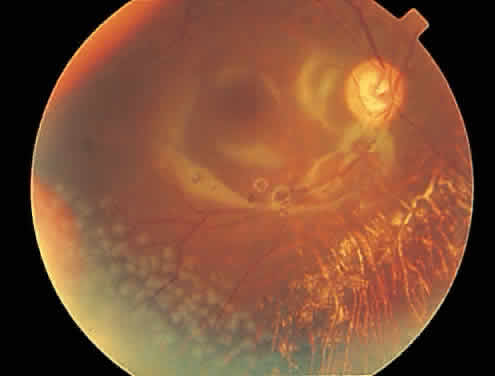

The hallmark lesion of CMV retinitis is a necrotizing, full-thickness retinitis that results in retinal cell destruction. CMV often initially affects retinal tissue adjacent to major retinal blood vessels or the optic disc (Fig. 1). This is consistent with the concept that the virus is spread to the retina hematogenously. In most cases, the pattern of infection is classic and distinctive, making clinical diagnosis straightforward. The area of active retinitis has a granular, dirty-white appearance. As the virus attacks the endothelial cells of blood vessels, hemorrhage is common. Advancement in the retinitis by both direct cell-to-cell transmission as well as spread by way of adjacent satellite lesions can be seen. Except for cases in which retinitis is acute, it is common to see areas of healed retinitis beside areas of active necrosis. Areas of burned-out necrosis show absence of any retinal tissue, whereas the underlying retinal pigment epithelium assumes a “salt and pepper” appearance. CMV retinitis can present initially as either large areas of retinal necrosis with hemorrhage or one or more small, focal areas of retinal whitening.1,12,14 These small, focal lesions may on occasion be confused with cotton-wool spots or lesions of toxoplasmosis.5,27 Unlike cotton-wool spots, focal areas of CMV may appear outside the posterior pole. These early, focal infiltrates of CMV may not be associated with retinal hemorrhages or vitreous cells.

Over a course that usually spans weeks, infiltrates of CMV tend to assume two different patterns of clinical disease.11,12 The first pattern is called hemorrhagic and is characterized by broad geographic zones of retinal whitening. These large, geographic lesions are usually in close proximity to a major retinal blood vessel or the optic nerve. Satellite lesions are common. When the retinal necrosis associated with CMV retinitis becomes widespread, it is almost invariably associated with retinal hemorrhages. Although the border between necrotic and unaffected retina is sharply demarcated, the border itself appears irregular and jagged. Exudation into the retina or subretinal space may be seen, adding to the granular appearance of the retinitis. Juxtaposition of large zones of white, granular necrosis with those of red retinal hemorrhage has led this appearance of CMV retinitis to be described as either “pizza-pie” or “cheese and ketchup.” The retinal blood vessels, both arteries and veins, in the areas of necrosis commonly appear sheathed, secondary to a vasculitis. As a consequence, secondary retinal vascular occlusions, especially branch retinal vein obstructions, may occur in the course of CMV retinitis. Immune-mediated vascular damage may play a role in the vasculitis.12 Central healing of these lesions will occur as the infection progresses. Avasculitis resembling “frosted branch angiitis” hasbeen reported (Fig. 2).28 A second pattern of CMVretinitis has been labeled “granular” or “brushfireborder.” In this appearance, the focal granular infiltrates enlarge slowly across a line, leaving ever-increasing areas of destroyed retina and atrophic retinal pigment epithelium behind. Hemorrhages and vitreous cells are a less prominent feature. There appears to be direct cell-to-cell transfer of infected virions in this pattern of infection (Figs. 3 and 4). The brushfire border is commonly seen in CMV retinitis lesions anterior to the equator (Fig. 5). The significance, if any, of these two clinical patterns of CMV retinitis is not known, and, in some eyes, both patterns of disease can be seen simultaneously or in sequence. Progression of retinitis has been defined in clinical trials as movement of a lesion border at least 750 μm along a front that is 750 μm or more in length, development of a new CMV lesion in a previously involved eye or in the uninvolved fellow eye of a patient with baseline unilateral disease.29 Without treatment or improvement in the host's immune system, CMV retinitis is a relentless, slowly progressive infection resulting in blindness caused by total retinal necrosis, retinal detachment, or optic nerve involvement, in any combination.